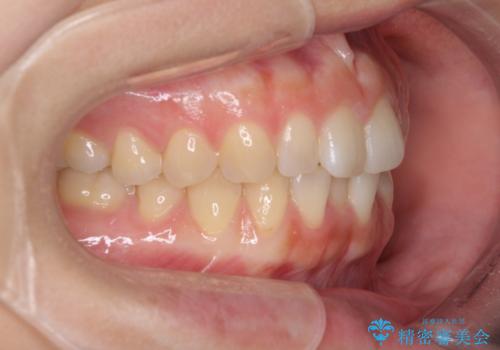

インプラントによる補綴治療とインビザライン矯正

- 抜歯が必要と診断された奥歯を気にして来院された患者様です。

抜歯の上インプラントによる補綴治療を行うこととなりましたが、前歯の叢生も気になるとのことで並行して矯正治療を行うこととしました。

歯列不正は軽微であったので、インビザラインによる矯正治療とし、矯正治療中にインプラント埋入を行う予定としました。

痛みがないので、ボロボロのまま放置していましたが、抜歯後は汚れが溜まりにくくなりスッキリとしたようです。

前歯のデコボコも解消され、ブラッシングが楽になりました。